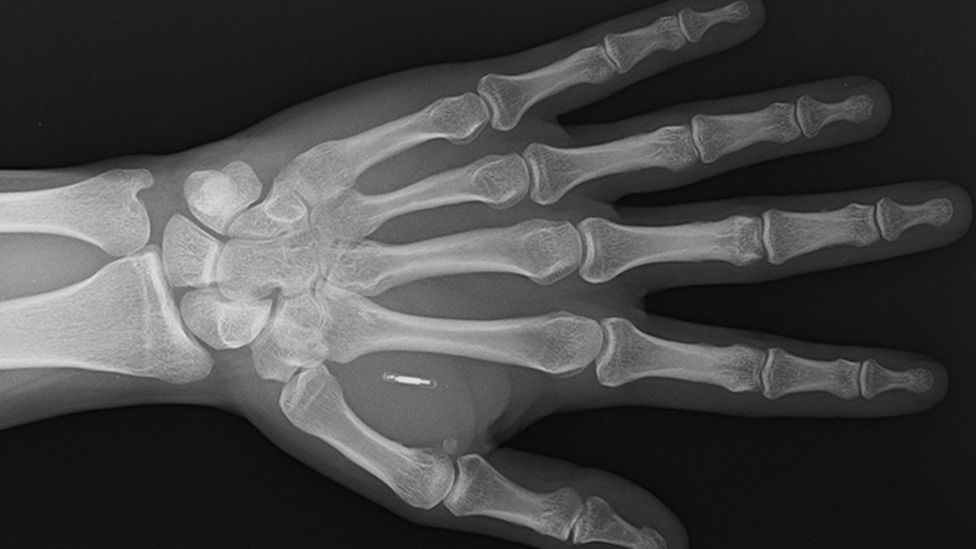

A Walletmor chipje, amely egy grammnál is kevesebb, és alig nagyobb, mint egy rizsszem, egy apró mikrochipből és egy biopolimerbe burkolt antennából áll, amely a műanyaghoz hasonló anyag.